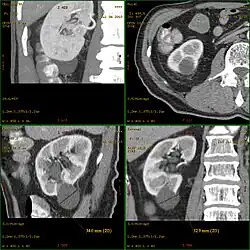

Klassifikation von Nierenzysten nach Bosniak

Die Einteilung von Zysten erfolgt nach der Klassifikation von Bosniak[2] in einfache und komplizierte Zysten:

- Typ III: Verdickung der Zystenwand oder der Septen, unregelmäßig oder körnig, gegebenenfalls mit Kontrastmittelaufnahme im CT. Bei diesem Erscheinungsbild kann eine Bösartigkeit (Malignität) nicht ausgeschlossen werden. Es kann sich aber auch um infizierte oder eingeblutete Zysten handeln.

- Typ IV: Eindeutig zystisches Malignom (Nierenkrebs) mit irregulären, soliden, kontrastmittelaufnehmenden Gewebsanteilen als Malignitäts-Kriterium.